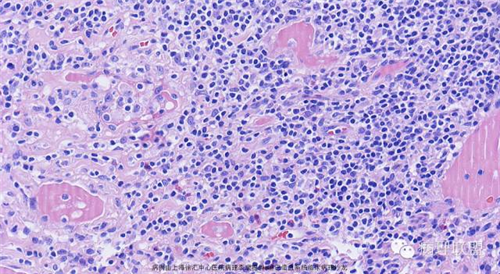

M,79岁,右半结肠粘膜下肿块。大小:6.5*6*6cm球形肿块,切面灰白质硬,界清。第一次取材。